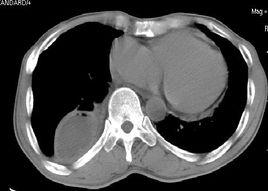

胸腔积液ct图片

胸腔积液ct图片讲解